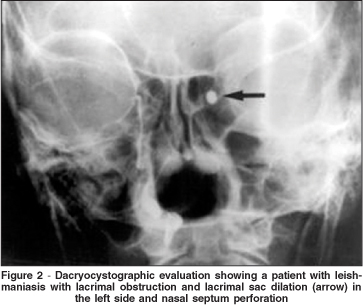

The nasolacrimal duct dilation was bilateral in 11 patients (22 nasolacrimal ducts) and unilateral in two (2 nasolacrimal ducts). Thus the dilated and permeable ducts were observed in 92.30% (24/26) of the lacrimal excretory systems evaluated by dacryocystography. The lacrimal sac was dilated in one patient (3.84% - 1/26) (Figure 2) and another (3.84% - 1/26) presented a nasolacrimal duct obstruction.

The main alteration observed in the lacrimal excretory system was a complete permeable lacrimal drainage tract with nasolacrimal duct dilation. Only one patient had lacrimal excretory system obstruction and lacrimal sac dilation.